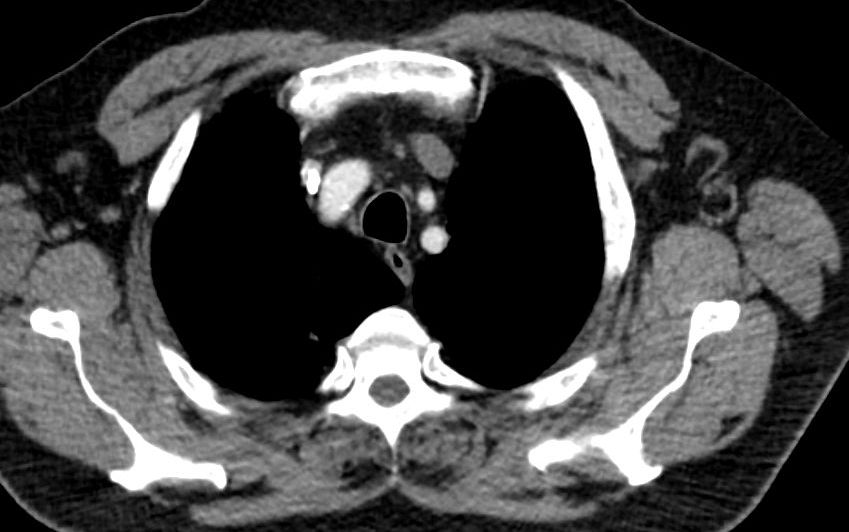

Lymphknoten Für jede Tumorentität sind regionale Lymphknotengruppen definiert. Diese bestimmen das N-Stadium. Lymphknotenmetastasen in nicht regionalen Lymphknotengruppen gelten als Fernmetastasen. In der linken Achselhöhle sind zwei vergrößerte Lymphknoten erkennbar, die eine zentrale Verfettung aufweisen und damit unverdächtig sind.